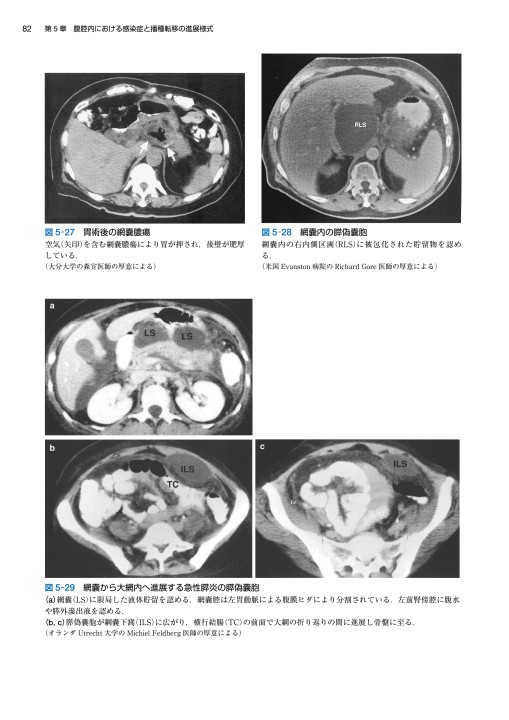

裁断済】マイヤース腹部放射線診断学 発生学的・解剖学的アプローチ。マイヤース腹部放射線診断学: 発生学的・解剖学的アプローチ。マイヤース腹部放射線診断学 発生学的・解剖学的アプローチ。mochi*°様✳︎ 小さなスコーンとポルポロン * スコーン 2月*。「マイヤース腹部放射線診断学 発生学的・解剖学的アプローチ」太田 光泰定価: ¥ 15400円+税即購入OKです(^^)・裁断済みです。書き込みはなく綺麗な状態です。裁断してある中古品であること、素人による裁断であることをご理解のうえ、ご購入下さい。神経質な方は購入をお控えください。・1-2日で発送致しますが、週末や連休中は発送が休み明けになることがあるかも知れません。。徹底的解剖学 | 黒澤一弘(かずひろ先生)による解剖生理学講座。綴じ口より裁断されておりバラバラの状態です。vol2 岩越真一先生(放射線医学 助教) | 奈良県立医科大学。グレイ解剖学 原著第5版 / Anatomy 今日も明日も/グレイ解剖学。裁断しているため、「傷や汚れあり」 にました。福井大学における革新的な画像医学教育への挑戦─ITとAiをベース。ポータブル電磁超音波探傷器 VOLTA2 (Innerspec Technologies。・ほとんど使用しておりませんが、多少のキズや小さな角折れ等あるかもしれません。黒澤一弘(かずひろ)解剖学IT教育・指圧師・ラダック on X。JRC2012 ziosoft/AMIN Seminar Report 超四次元画像。・梱包は丁寧に行うようにしておりますが、配送中の破損は保証できませんので、ご了承下さい。徹底的解剖学 | 黒澤一弘(かずひろ先生)による解剖生理学講座。画像診断を学ぼう 単純X線からCT・MRI・超音波まで 第2版。その際はご容赦下さい。【裁断済】小児・成育循環器学 改訂第2版